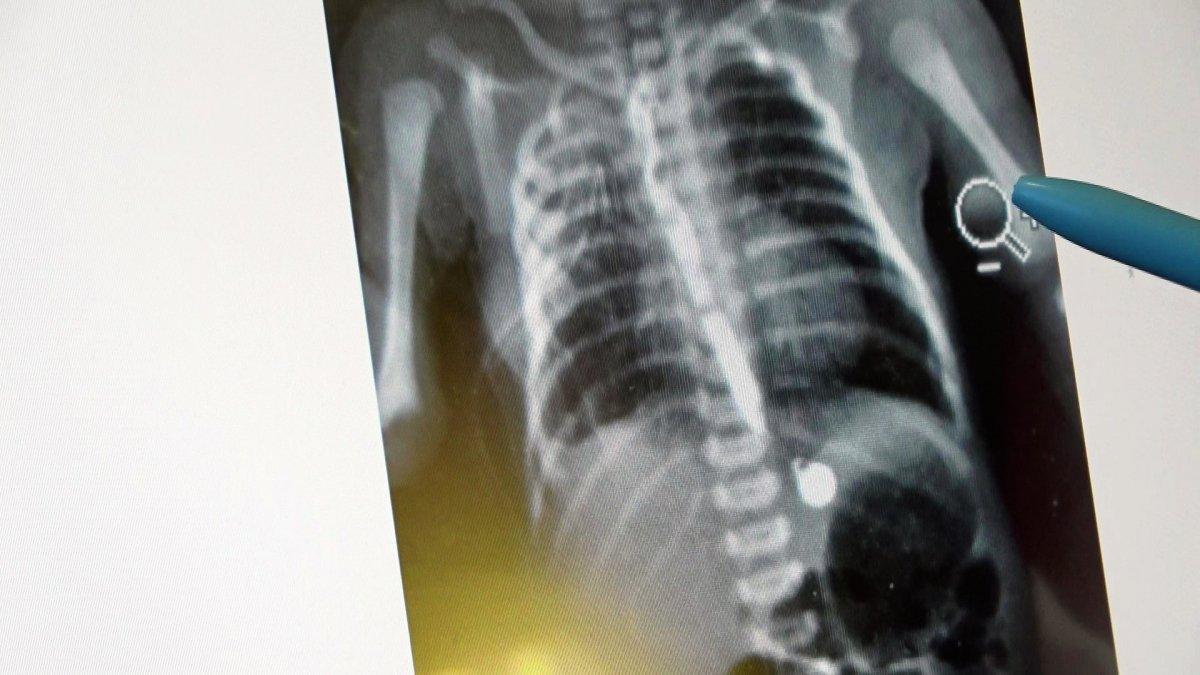

Aile, erken müdahale edilmediği takdirde çocuklarının öleceği gerçeği ile karşı karşıya kaldı. Kaya ailesinin başvurduğu özel hastanede, Çocuk Cerrahisi Uzm. Opr. Dr. Ayşe Bahar Edirne ve keibi tarafından bebeğin 3 santimetre olan yemek borusu ameliyatla 15 santimetreye çıkarıldı.

“Bebeğimiz doğduğunda yapılan ön tetkiklerde yemek borusunun olmadığı anlaşıldı. 2-3 günlük olduktan sonra ameliyatını gerçekleştirdik. 15 gün sonrasında da ağızdan beslemeye başladık. Yemek borusunun oluştuğunu çekilen filmlerde tetkik ettik. Sonrasında da ailesinin yanına verdik. Kontrolleri yapıldığında ise hiçbir problemi olmadığı görüldü. Eğer bu hastalık tespit edildiğinde zamanında tedavi edilmezse yemek borusu olmadığı için bebeğin beslenme şansı olmuyor. Ondan sonra da maalesef yaşama şansı olmuyor. Bu hastalık acil tedavi edilmesi gereken bir sorun.

Öncelikle ultrason ve ön tetkikler yapılıyor. Bütün hazırlıklar yapıldıktan sonra özellikle yeni doğan yoğun bakımın olduğu bir donanımlı bir hastanede bakımının yapılması gerekiyor. Ameliyat da başarılı geçtiği takdirde bu şekilde doğan bebekler hayata tutunuyorlar. Ameliyat yapılmazsa yaşama şansı olmayan bir hastalıktır. Binde bir ihtimalle karşımıza çıkıyor.”